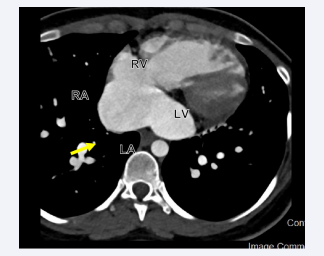

Patient was taken to the catheterization laboratory for ASD secundum type closure using Amplatzer device under TEE guidance. However, during procedure the multipurpose catheter crossed very inferiorly at the level of the coronary sinus (CS) into the LA. The left upper pulmonary vein identified very easily as well as a small CS vein, which is draining from the great cardiac vein. TEE showed that the multipurpose catheter in the LA, however, it did not go through the previously mentioned secundum ASD, raising the possibility of different co-existing septal defect. Procedure was aborted and patient was scheduled for CCTA to better define the septal defect and rule out the presence of PLSVC. CCTA showed a large ASD inferiorly, representing an UCS. The defect is large, measuring 24 mm in length, and both the superior and inferior vena cava are intact. The pulmonary veins drain in the LA. The right pulmonary veins emerge from a single trunk, while the left pulmonary veins emerge from a very short trunk that splits into two branches early on (Figures 6-9).

Cardiac computed tomography angiography (CCTA) in  axial display showing a communication between the RA and LA  representing ASD.

Figure 6: Cardiac computed tomography angiography (CCTA) in axial display showing a communication between the RA and LA representing ASD.

Cardiac computed tomography angiography (CCTA) in  sagittal displays showing dilated RA, ASD (Yellow Arrow), and  unroofed CS (Red arrow).

Figure 8: Cardiac computed tomography angiography (CCTA) in sagittal displays showing dilated RA, ASD (Yellow Arrow), and unroofed CS (Red arrow).